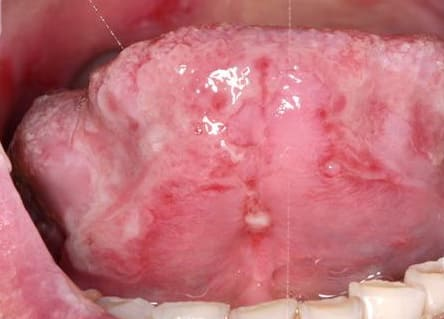

Pemphigus Mucosae = فقاع الاغشية المخاطية